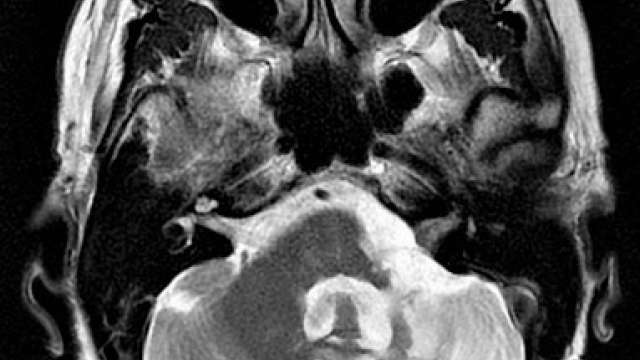

Brain & Spine Tumors

The UCLA Department of Radiation Oncology treats both malignant brain cancer and benign tumors.

Brain Metastases

At UCLA, Radiation therapy is an important tool to relieve the symptoms associated with metastatic cancer.